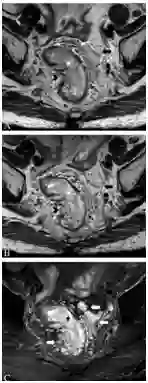

T2加权像粘液性肿瘤呈明显高密度信号,外周蕾丝样增强。MRI检查缺点如下:粘液性肿瘤弥漫性浸润生长已传播至肠壁外,而肠壁解剖结构仍完整;放化疗后即便已无肿瘤、唯留粘液湖时,粘液性肿瘤仍倾向于保持高密度信号(图8);粘液性肿瘤T2加权像呈水样高密度信号,而周围盆腔脂肪也是高密度信号,因此薄层高分辨非压脂轴位T2加权像很易漏诊,此时需调整MRI参数,采用T2加权压脂像抑制脂肪信号,或非压脂轴位T2加权像采用二种不同高回波时间(TE)检测肿瘤,因为周围盆腔脂肪产生二种不同的密度信号(图9)。

图8  65岁女性直肠粘液腺癌放化疗后,轴位T2加权像显示直肠壁粘液池高密度信号(长箭头)和直肠系膜淋巴结(箭头),较前无显著变化,临床定义为无治疗反应,但术后病理证实为粘液池,未见肿瘤细胞。

图9  直肠粘液腺癌。TE 80ms(9A)和120ms(9B)轴位T2加权像显示直肠腔内粘液腺癌不同的高密度信号(星号),右侧肠壁(箭头)和左侧直肠系膜(长箭头),二种TEs信号差别有助于肿瘤检测。9C显示轴位T2加权压脂像,方便检测肿瘤(星号)和肿瘤播散(长箭头)。